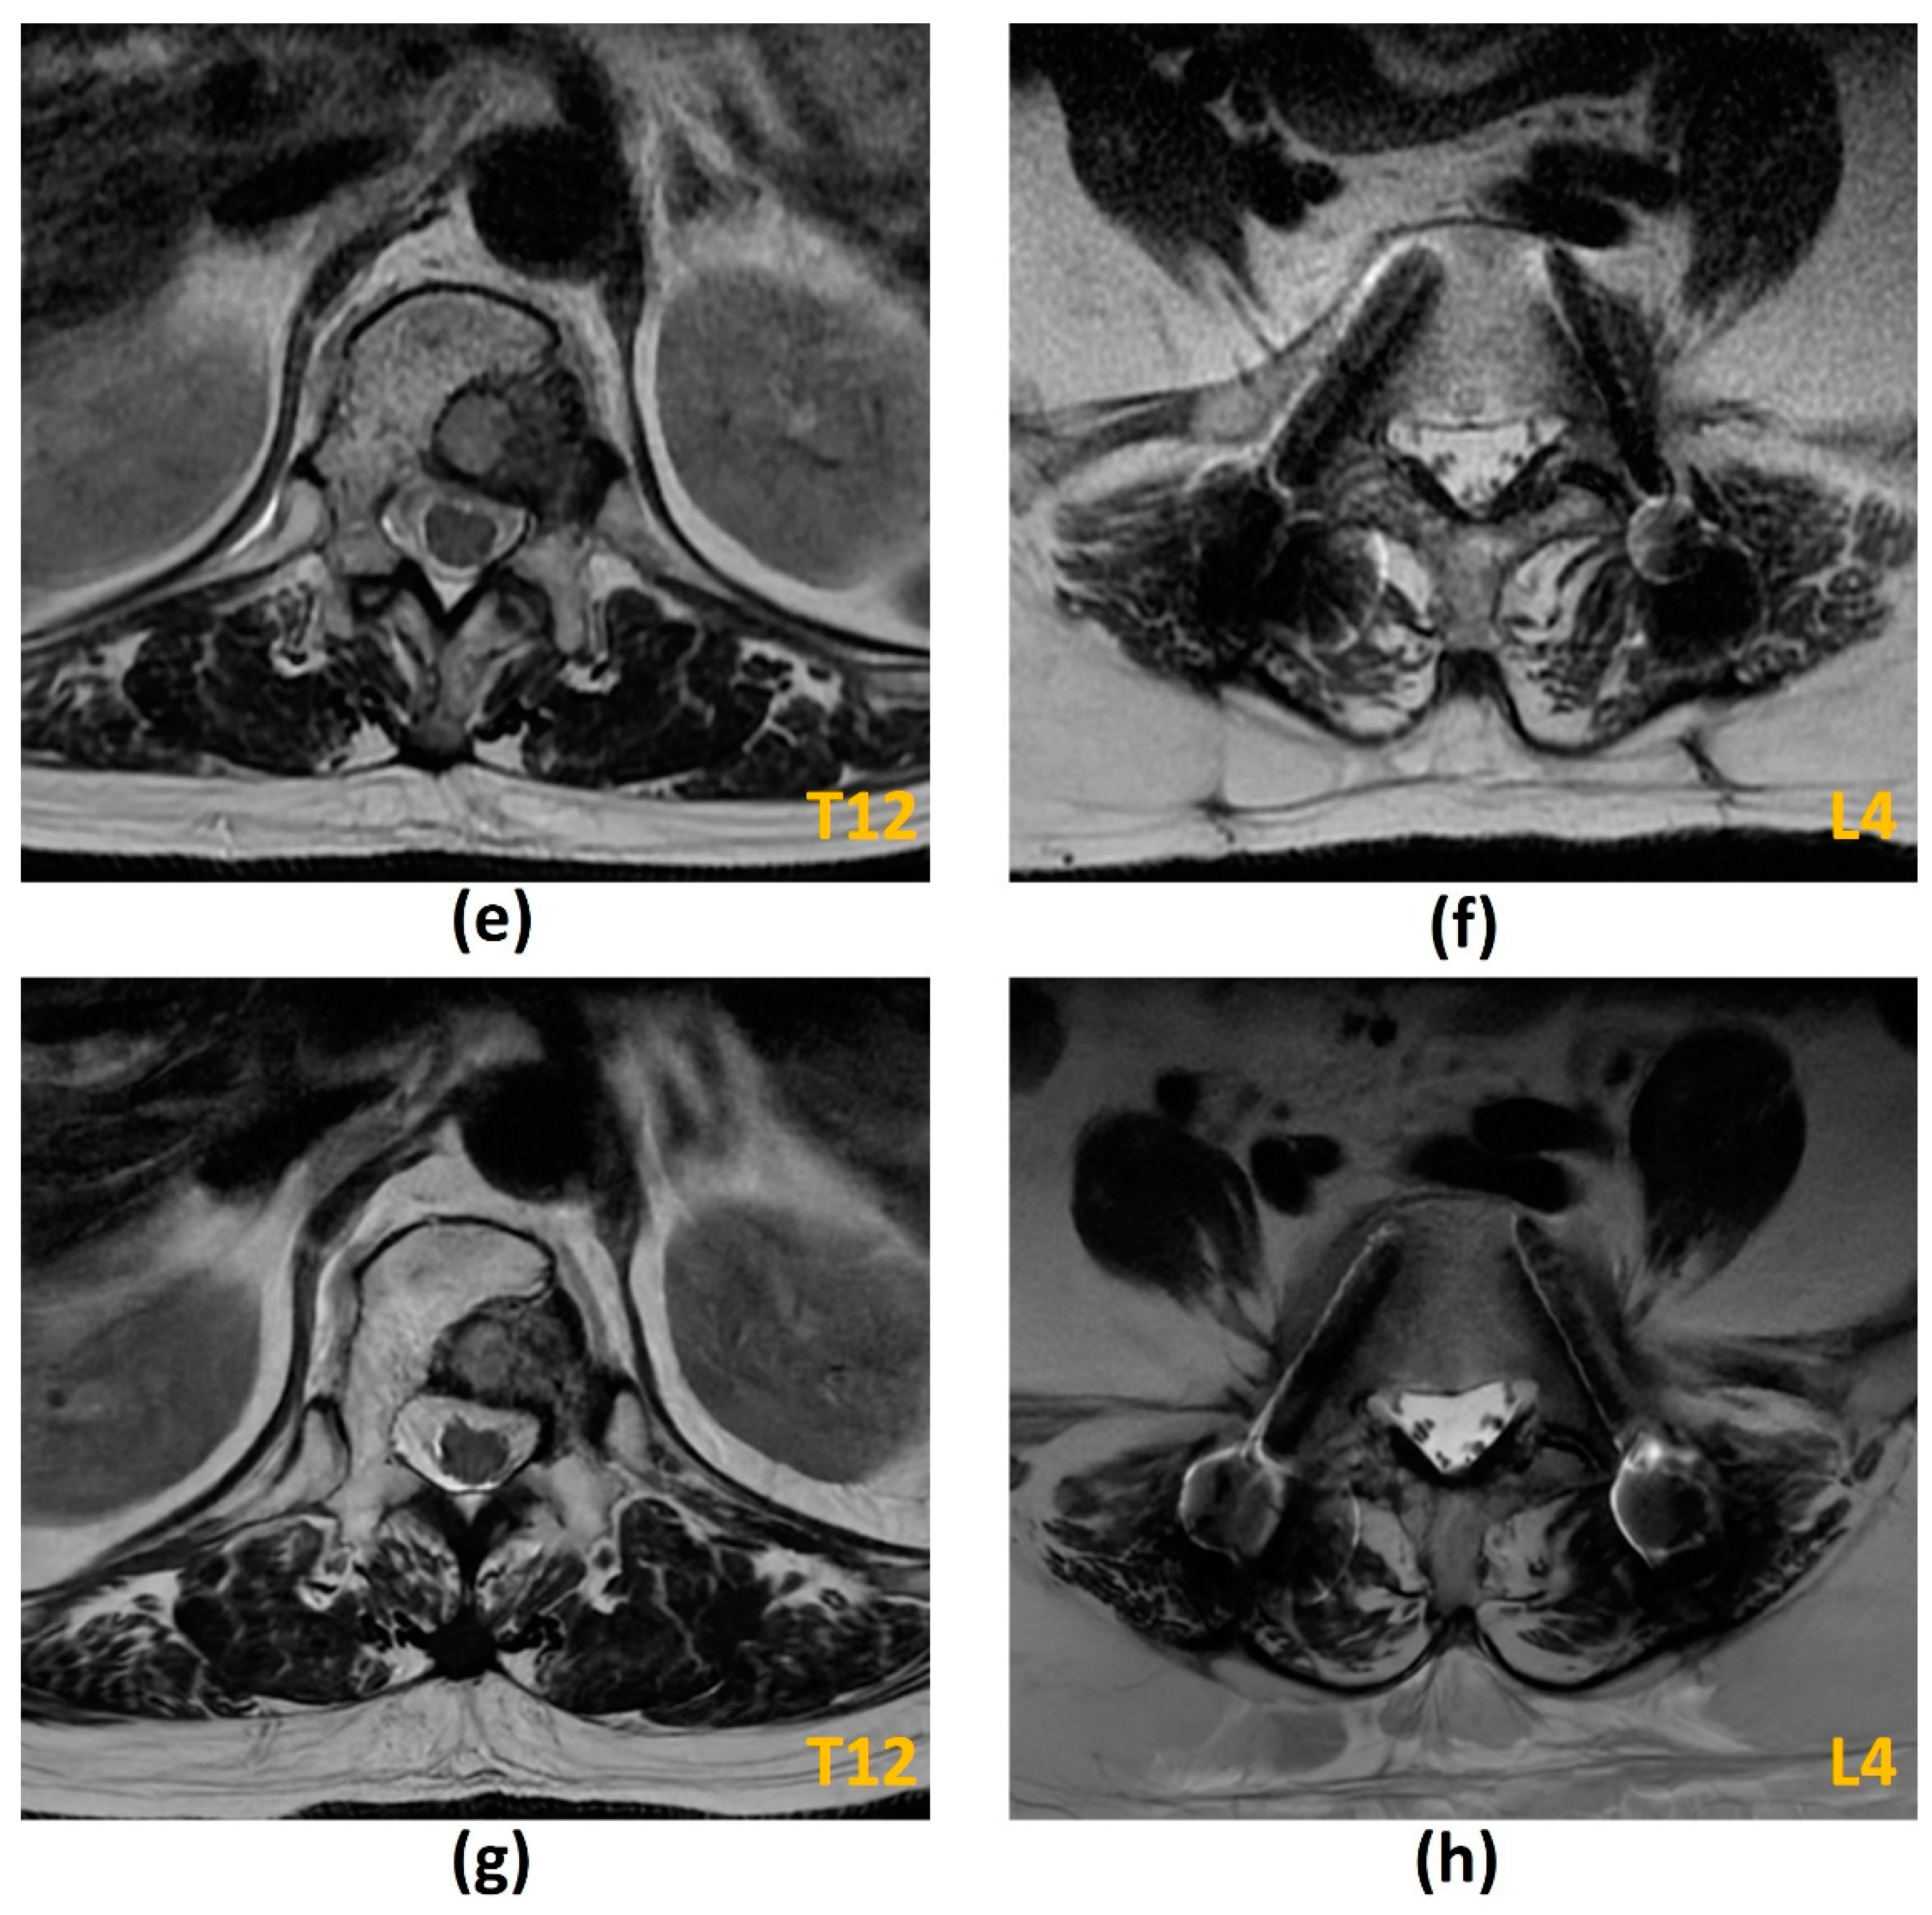

| T2-W | Evaluation of spinal cord and nerve root compression (‘myelogram-like effect’); Detection of cord signal changes (e.g., myelomalacia or oedema) | Suboptimal for evaluation of marrow replacing lesions |

| T1-W | Identification of marrow replacing lesions including metastasis; Useful for comparison with post-contrast sequences to identify true contrast-enhancement | Suboptimal for evaluation of spinal cord and nerve root compression; Peritumoural oedema may also appear hypointense on T1-W sequences, which may limit the accuracy of measurement of the true tumour size |

| T1-W post-contrast FS | Detection of enhancing vertebral metastasis, sites of leptomeningeal and intramedullary disease; Delineation of tumour extent including identification of the epidural component, and presence of foraminal or paraspinal extension; Determination of biopsy site of highest yield (if biopsy required) | Suboptimal for evaluation of spinal cord and nerve root compression |

| STIR | Identification of marrow replacing lesions including metastasis; More accurate measurement of true tumour size from surrounding peritumoural oedema than T1-weighted sequences; Identification of macroscopic fat in lesions | Suboptimal for detection of sclerotic vertebral metastasis without oedema |